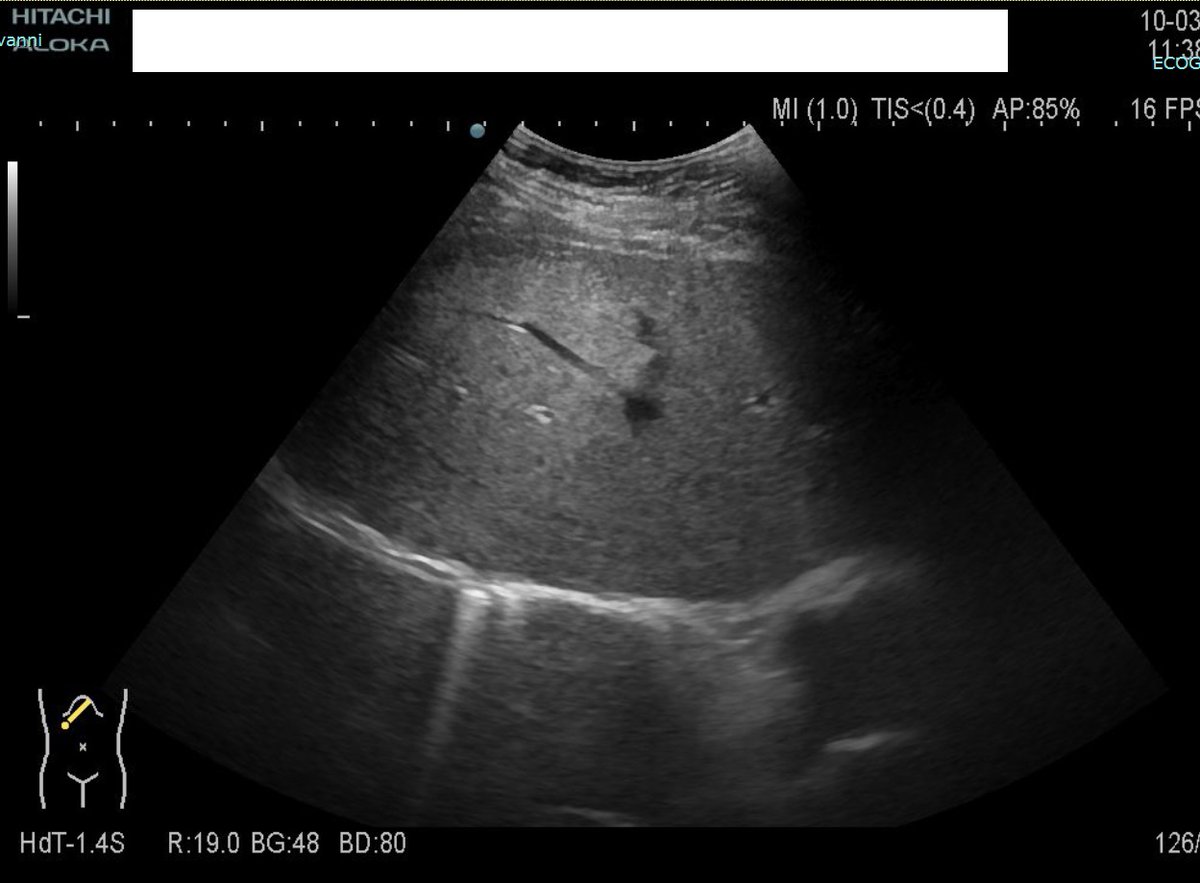

Below an example in a 53y man with large areas of focal steatosis results of massive portal thrombosis (Antiphospholipid syndrome).